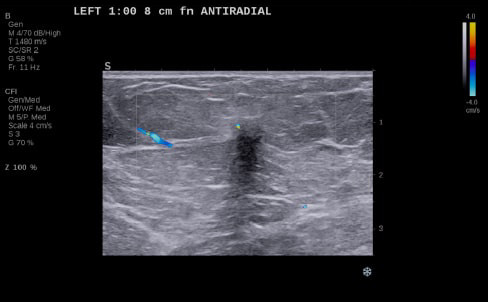

Case Example 5:

59-year-old female presents with a new mammographic asymmetry on the left breast.

A 1.2 cm mass is seen on ultrasound with some doppler signal along periphery of mass.

Case Example 5: Observations

With OA imaging we can see negative internal findings but positive external features in the boundary and peripheral zones.

We can see feeding and draining vessels or “whiskers” in the boundary and peripheral zones on OA.

Radiating vessels continue from the peripheral zone into the boundary zone and count as features in both zones.

Invasive Ductal Carcinoma Grade I

- ER+

- HER2-

- PR-

- Ki67=10%

The mass was up-classified to BI-RADS 5. Unlike TNC, luminal A masses typically present with external features in the boundary and peripheral zones and no OA internal features. Typically, luminal A masses have a low Ki67 and tend to have less internal angiogenesis and deoxygenation.